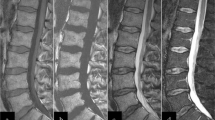

Based on the results of a control cohort, the enhancement of normal bone marrow showed great variations between 3% and 40%, mean 17% (in adults age >40 years) (Baur et al. 1997) (Fig. 20.1). This is explained mainly by the variations of the fat cell content in normal marrow interindividually and the changes that occur during aging with an increase of fat. Patients with lower fat content, mainly younger patients, show a stronger gadolinium enhancement than individuals with a higher fat cell content. In another study gadolinium enhancement was correlated to the grading of diffuse infiltration, neovascularization of bone marrow, and the fat/hematopoietic cell content in myeloma (Baur et al. 2004). In myeloma patients with an intermediate- or high-grade diffuse infiltration of the bone marrow, mean enhancement was significantly higher than in normal bone marrow (p < 0.0001). Also in patients with low-grade diffuse infiltration, gadolinium enhancement was significantly higher than in normal bone marrow (p < 0.01) but showed a strong overlap with normal bone marrow (Table 20.1). As a simple rule it can be stated that if the percentage increase of signal exceeds the limit of 40% in patient older than 40 years, this can be considered as pathologic. The reasons for increased enhancement in diffuse infiltration by myeloma were an increased microvessel density, increased cellularity, and a decreased fat cell content (Vacca et al. 1994; Aguayo et al. 2000; Rajkumar et al. 2000; Baur et al. 2004). The fluent transitions of the plasma cell content, the fat cell content and the microvessel density, as well as the fact that all three parameters contribute to contrast enhancement explain that no definite cutoff values can be found for contrast uptake in diffuse infiltrating multiple myeloma. In addition, the percentage signal increase after gadolinium administration does not reflect an absolute value of perfusion, since the contrast media diffuses quickly into the extracellular space.

To measure the gadolinium enhancement of the bone marrow, the MRI examination protocol should include sagittal T1-weighted SE sequences without fat saturation before and after intravenous gadopentetate dimeglumine (Gd-DTPA) administration (0.1 mmol/kg body weight, 0.2 ml/kg). The contrast medium should be given as a bolus injection followed by a saline flush. Scan parameters on the pre- and post-contrast T1-weighted SE sequences have to be identical; the values for receiver and transmitter adjustments have to be kept constant.

SI measurements should be made with circular region of interests placed in three vertebral bodies of the lumbar spine. The mean value should be calculated from the three measurements to compensate for SI differences within the bone marrow depending on changes in the ROI’s position. Avoid placing the ROI’s in midsagittal slices with basivertebral veins. The ROIs have to be placed in identical positions of the vertebral body on T1-weighted images before and after injection of contrast material (Fig. 20.2). The percentage SI increase is calculated as follows:

T1-w SE image (TR/TE 572 ms/15 ms) pre- and post-contrast in a patient with diffuse infiltration by myeloma. The regions have to be placed in identical positions in lumbar vertebral bodies. Mean signal intensity increase can be calculated. An increase of more than 40% in adults (>40 years) is indicative of diffuse infiltration